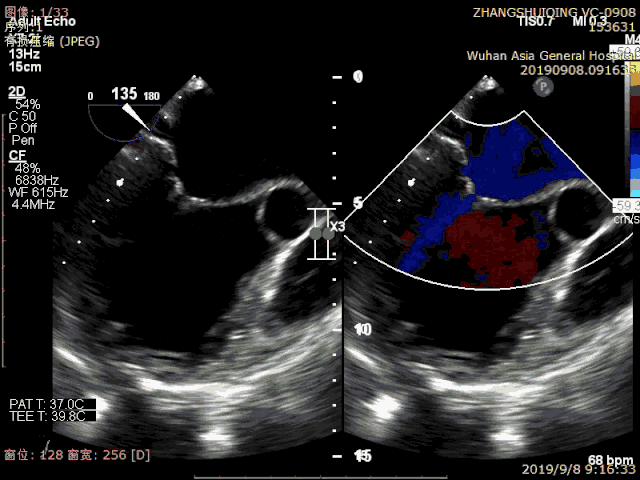

ValveClamp是我国自主研发的首个进入上市前临床试验的二尖瓣反流微创介入治疗器械,其手术是一种“在跳动的心脏上完成的超微创手术”,先在心前区切开3cm切口,在心脏超声指导下穿刺心脏送入器械进行手术操作。该手术具有创伤小,无需心脏停跳及体外循环,故安全性更高,尤其适合于无法耐受传统外科手术的老年患者。

患者术前心超显示极重度反流